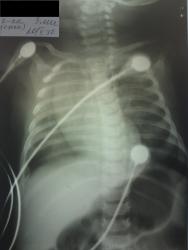

Вот сегодня сделали контроль сегодня. На мой взгляд явная положительная динамика. И ребра все целы. Скорее всего будет пневмония. В ОАК повышается СОЭ, лейкоцитоз со сдвигом влево...

Динамика положительная лишь в том, что разрешился ателектаз. Справа, думаю, сейчас есть пневмония. А по первым снимкам - ребенок, конечно, сильно развернут, но даже для такого разворота очень выраженное смещение срединной тени, значит, был ателектаз. На счет пневмоторакса - не знаю, сложно сказать был или нет, я бы на тот момент сделала прямую рентгенограмму, но на левом боку, чтоб четко отдифференцировать, пневмоторакс это или нет. Кстати, перелом ребер совсем не обязателен, чтоб возник пневмоторакс у новорожденного. По поводу срединной тени - это вилочковая железа.